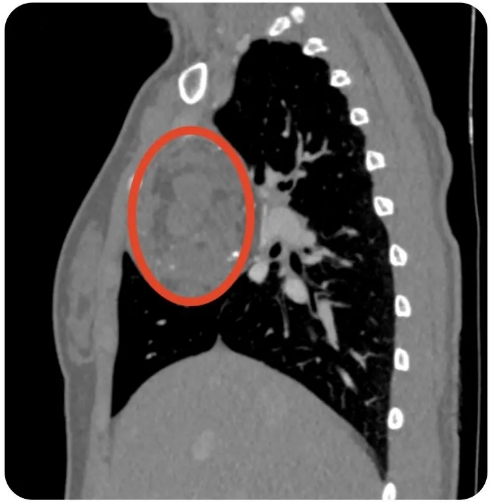

日前,心胸外科赵志宏主任团队借助胸腔镜,为一位年仅17岁的前纵隔畸胎瘤患者成功实施微创手术,巧妙摘除直径约8.0厘米肿瘤,在解除致命威胁同时,还避免了传统切口的创伤和长疤痕。

一个月前,17岁的小刘,经体检CT检查发现胸腔有一直径约8.0厘米的肿瘤。“一点感觉都没有,怎么会生这么大的肿瘤?”小刘在家属的陪伴下,一家人心急如焚地找到鄂州市中心医院心胸外科赵志宏主任。

赵主任根据肿瘤部位及影像学特征,考虑最常见的情况就是畸胎瘤。“小刘的肿瘤巨大且位置较深,紧贴心脏、上腔静脉、头臂静脉等重要器官及血管,容易出现判断差错造成误损伤,且部分区域无法到达,要将深藏在狭窄缝隙中的肿瘤摘除,手术过程堪比拆弹”,赵志宏主任说。经过综合考量,胸外科赵志宏主任团队决定开展微创胸腔镜纵隔肿瘤切除术,这样可以避免胸骨切开,同时为手术操作提供了宽阔清晰的视野。